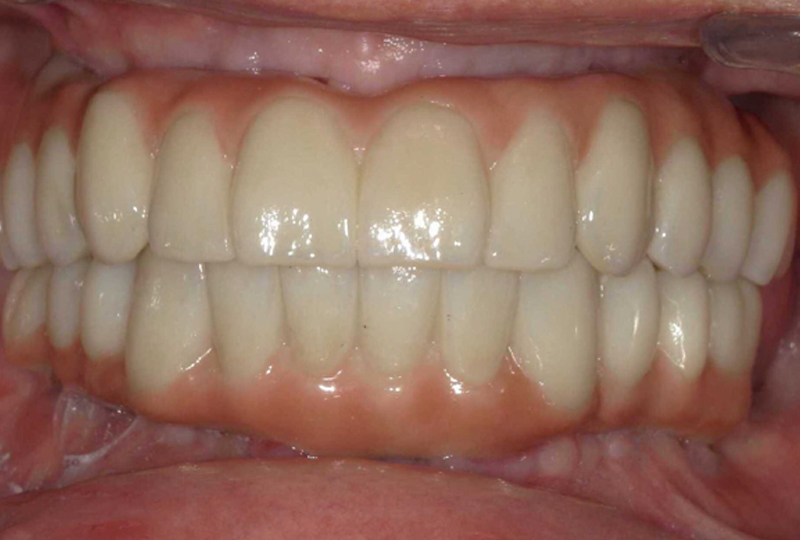

Con questo materiale raccolto si ricostruiva il paziente virtuale nel software CAD (Rijeka®, Exocad). Le arcate dentarie venivano inserite nell’articolatore virtuale (Figura 12) e successivamente venivano progettate le protesi definitive seguendo gli stessi criteri estetici ed occlusali delle provvisorie, ovvero:

- Il margine incisale dei centrali era posizionato con un'esposizione di circa 2 mm dal labbro superiore a riposo e, a livello antero-posteriore, sul confine del vermiglio del labbro inferiore.

- La linea mediana era posizionata a metà della distanza compresa tra le commessure labiali.

- Il piano occlusale frontale dell'arcata superiore era reso parallelo al piano bi-pupillare.

- Il piano occlusale antero-posteriore dell'arcata superiore era reso parallelo al piano di Camper.

Le protesi definitive venivano prodotte in zirconia multilayer (ZOLID-GEN X 1100±150®, AMANN GIRRBACH) infiltrata e colorata con ceramiche fluide (MIYO®) sia nella parte bianca che in quella rosa. I T-base di connessione venivano incollati nel corpo protesico senza utilizzare nessun modello in gesso di riferimento. Nel terzo e ultimo appuntamento consegnavamo le protesi definitive (Figure 21,22,23).